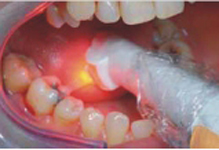

FotoSan 360

Přístroj na principu světlem aktivovaná desinfekce neboli fotodynamická antimikrobiální chemoterapie. Přístroj s okamžitým účinkem ničí veškeré mikroorganismy bez jakýchkoli vedlejších účinků. Jedná se o bezbolestné ošetření, které nevyžaduje anestezii, nemá vedlejší účinky a ničí 99% bakterií. Používá se především v parodontologii a implantologii při léčbě zánětů v okolí zubů a implantátů (dezinfekce tzv. chobotů), záchovné stomatologii (ošetření kazů) i endodoncii (dezinfekce kanálků zubu).